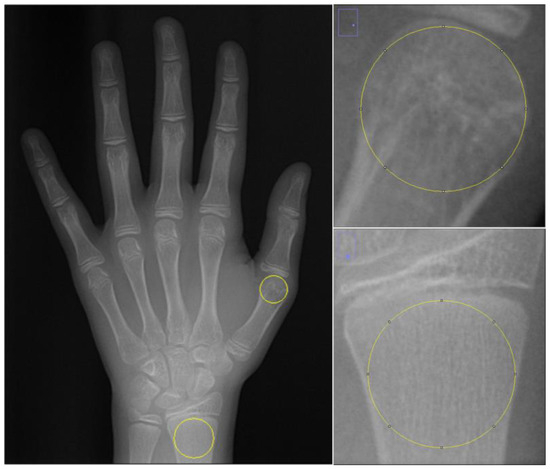

2.2. Fractal Analysis

2.3. Region of Interest Selection